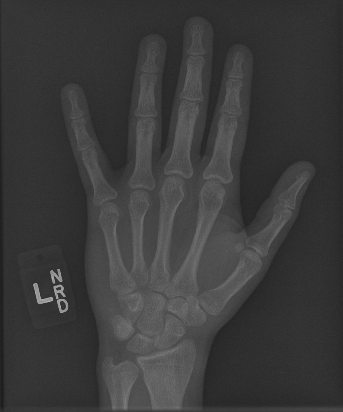

In this work, we focus on a subset of the MURA dataset [17] containing only hand images. In total, we have 5,543 images of 2,018 studies of 1,945 patients. Each study is labeled as negative or positive, where positive means that there was an anomaly diagnosed in this study. There are 521 positive studies, with a total of 1,484 images. Figure 1 shows some examples from the dataset. In summary, our contributions are as follows:

The first step in our pipeline is to detect the X-ray image carrier in the image. To this end, we apply OpenCV’s contour detection using Otsu binarization [14], and retrieve the minimum size bounding box, which does not need to be axis-aligned. This works sufficiently well as long as the majority of the image carrier is within the image (cf. Figure 3). However, the approach might fail for heavily tilted images or those where larger parts of the image carrier reach beyond the image border.

Hand Localization

To further improve the detection of hands, and in particular split the images where two hands are depicted on one image, we manually labeled approximately 150 bounding boxes in the images. Using this small dataset, we fine-tune a pre-trained single shot multibox detector (SSD) [12] with MobileNet as taken from TensorFlow. An exemplary results can be seen in Figure 3.

Foreground Segmentation

In a final step, foreground segmentation is performed using Photoshop’s "select subject" method in batch processing mode. Thereby, we obtain a pixel-wise mask, roughly encompassing the scanned hand.